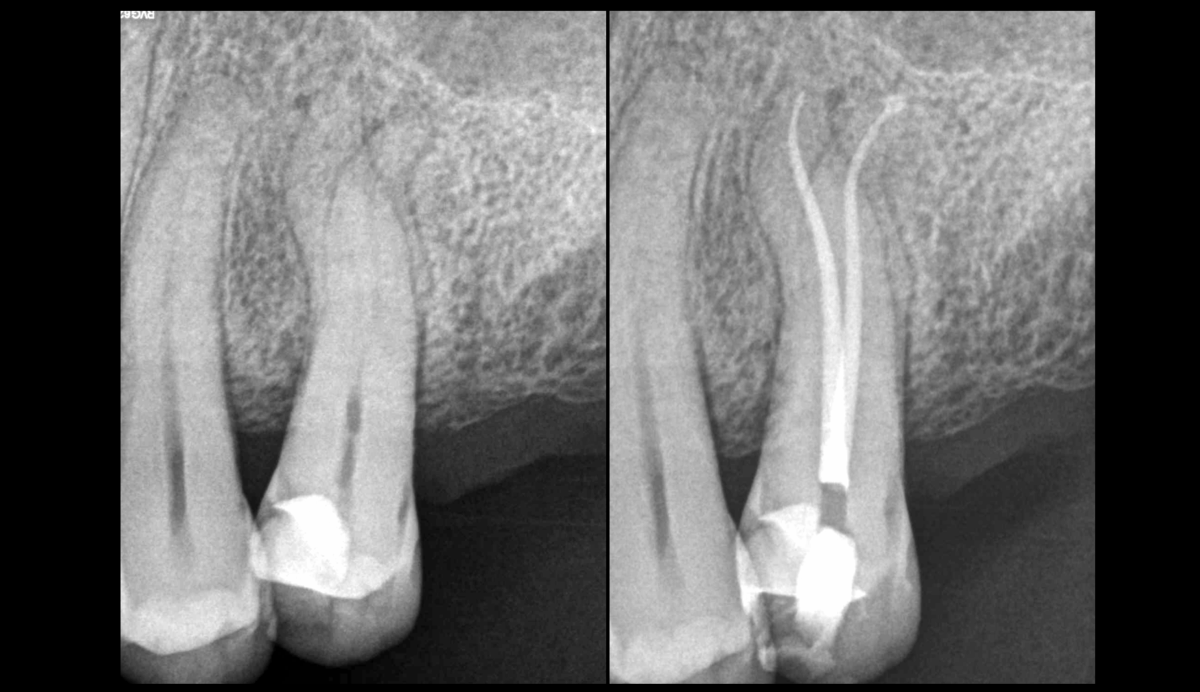

🎯 Courbures légères & oblitérations canalaires

🦷 Utilisation de limes manuelles 6, 8, 10 courtes d’abord (𝟐𝟏𝐦𝐦), puis longues.

🔄 𝐌𝐨𝐮𝐯𝐞𝐦𝐞𝐧𝐭 𝟏⁄𝟒 𝐝𝐞 𝐭𝐨𝐮𝐫, 𝐞𝐧 𝐩𝐫𝐞𝐬𝐬𝐢𝐨𝐧 𝐚𝐩𝐢𝐜𝐚𝐥𝐞 𝐥𝐞́𝐠𝐞𝐫𝐞, 𝐩𝐮𝐢𝐬 𝐫𝐞𝐭𝐫𝐚𝐢𝐭.

🔁 2 à 3 mouvements par lime ➡️ puis changement de lime pour un diamètre supérieur.

💧 Après la 10 : irrigation, puis retour à la lime 6.